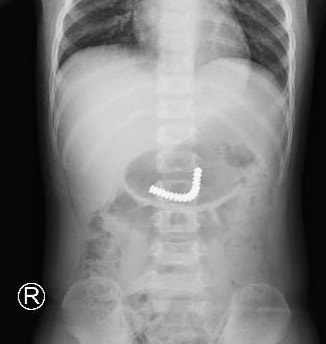

Khi đang cầm máy massage của mẹ, bé T.H.S., 3 tuổi, ngụ quận 8, TP.HCM, đã nuốt tất cả viên nam châm trong máy vào bụng. Tại Bệnh viện Nhi đồng Thành phố (TP.HCM), các bác sĩ nhanh chóng cho bé chụp X-quang và phát hiện dị vật trong dạ dày. Bệnh nhi được chỉ định nội soi tiêu hoá khẩn. Lúc này, dị vật đã di chuyển xuống ruột non.

Ngay lập tức, các bác sĩ khoa Ngoại Tổng hợp quyết định khẩn trương mổ nội soi thám sát ổ bụng. Kíp mổ nhẹ nhàng mở vết mổ ngay rốn và đưa đoạn ruột phình chứa dị vật đến khu vực mổ. Đoạn ruột được mở hỗng tràng và lấy ra 18 viên nam châm dính kết chùm lại. Sau phẫu thuật, bệnh nhi hồi phục tốt và dự kiến xuất viện sau vài ngày tới.

Chuỗi nam châm trong ruột bé trai hiển thị trên phim X-quang. Ảnh: Phương Vũ.